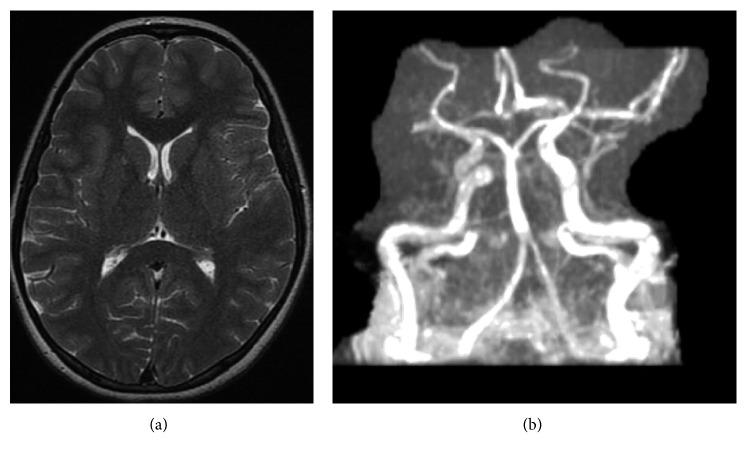

We present the case of a 15-year-old Caucasian girl with a history of chronic recurrent multifocal osteomyelitis and ulcerative colitis presenting with hypertensive emergency secondary to Takayasu's arteritis with middle aortic syndrome. She was treated with corticosteroids and methotrexate and ultimately required infliximab infusions of 15 mg/kg every 4 weeks to successfully control her symptoms and normalize her inflammatory markers.

我们报告一例15岁白种女孩的病例,她有慢性复发性多灶性骨髓炎和溃疡性结肠炎病史,因高安动脉炎合并中主动脉综合征继发高血压急症。她接受了皮质类固醇和甲氨蝶呤治疗,最终需要每4周输注15mg/kg英夫利昔单抗以成功控制症状并使炎症指标恢复正常。